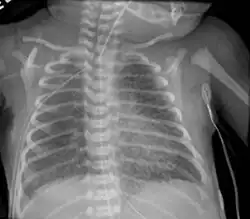

| Chest radiography showing severe pulmonary interstitial emphysema | |

A chest X ray may show a "salt and pepper" appearance due to the linear lucencies that are present.